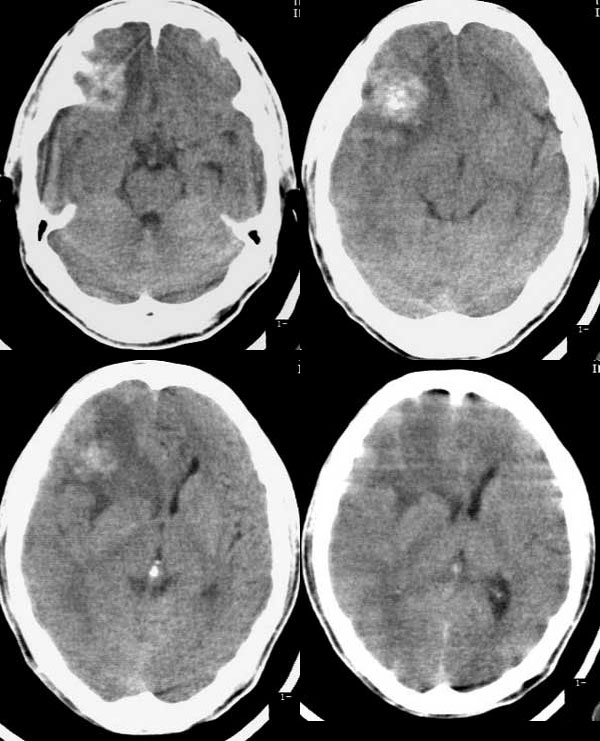

CT00236:颅内病变

结果公布:http://www.radida.com/bbs/forum. ... =1&toread=1#tpc m48,反复头痛半月,四肢抽搐一天。

右额叶血管畸形,海绵状血管瘤。

右额叶血管畸形。

血管畸形伴出血有可能,因为出血水肿期可以有占位。

当然胶质瘤也不能排。mri吧。